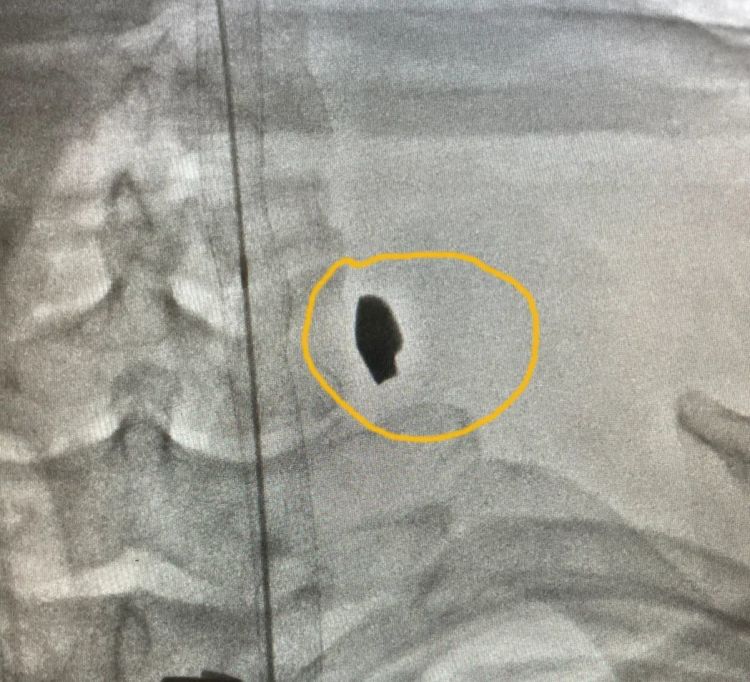

不到1厘米的颈部“小伤口”

近日一个黄昏,陈先生看人修车时,突然感觉颈部左侧一痛。他下意识地用手一按,手上是一抹鲜血。

旁人也发现了陈先生的异常,告诉他,颈部有一个不到1厘米的伤口 ,正在渗血。

陈先生被快速送到温岭当地医院。CT检查发现,他的颈动脉破裂,正在往外冒血,大部分血液滞留在颈部,脖子被撑得粗了一圈 。